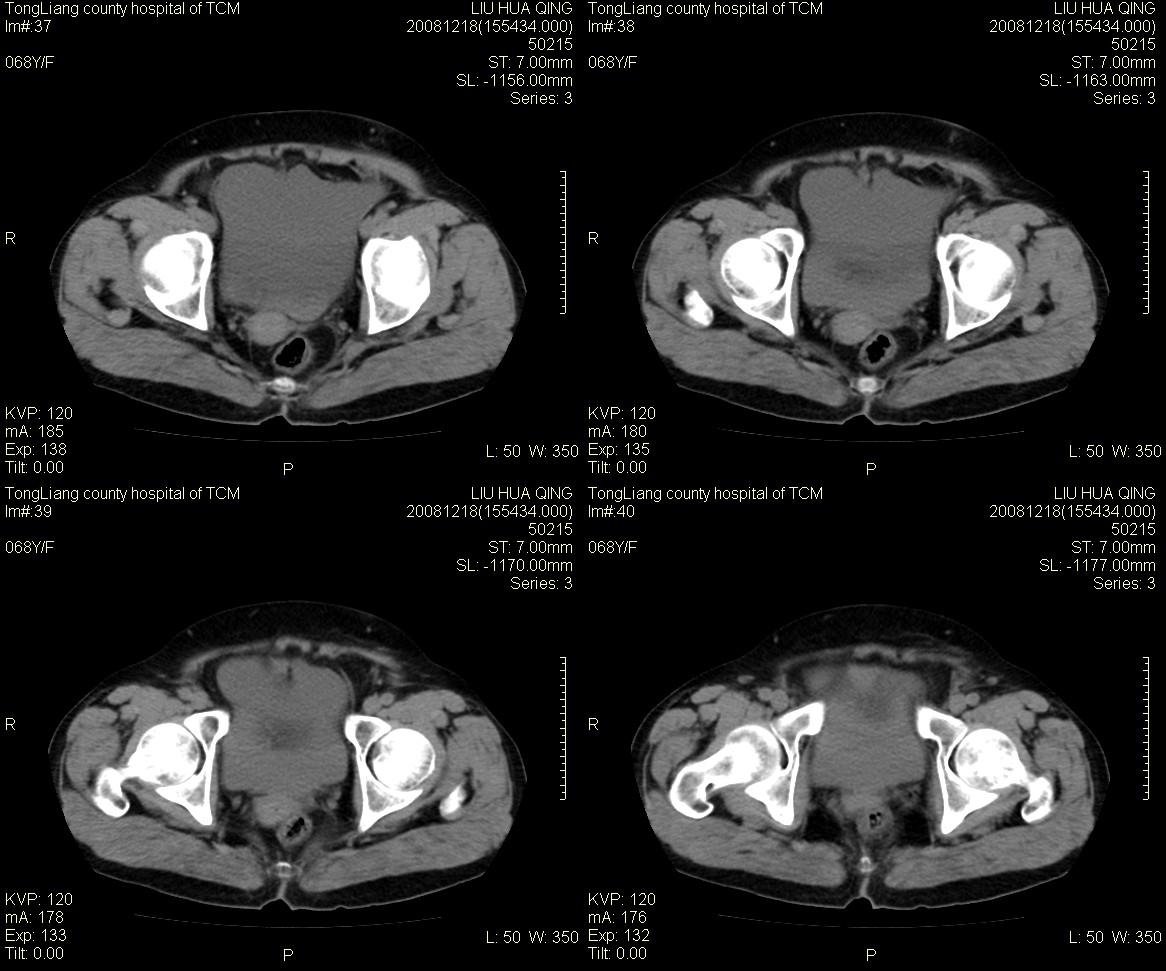

女,68y,下腹疼3月,一月半前院外ct示上腹未见异常。近1月来,症状加重。4天前入院,b超示胸腹水。今日呕吐频繁。  生化检查:  结核抗体阴性,血沉18mm/h, 癌胚抗原阴性,胸水细胞学检查见多数淋巴细胞。 白细胞总数5.4x10^12/l,血红蛋白104g/l.

患者右中腹部肠管聚集,内密度不均,可见片絮状及结节样增密影,小肠壁增厚,与之相邻处有软组织影。

腹腔积液可以肯定,原因?右侧下腹肠壁增厚,周围脂肪密度增高,粘连坏死?---梗阻坏死(不像)还是血栓坏死,占位?期待结果。

1)右侧腹腔前部见类似“网膜饼”样改变,考虑网膜转移瘤。2)腹水。

腹膜污染[大网膜增厚可见污垢征及小班结与饼片影,肠系膜增厚],大量腹水。考虑癌性腹膜炎,建议查腹水。结核待排.注意上腹部及胃肠道检查